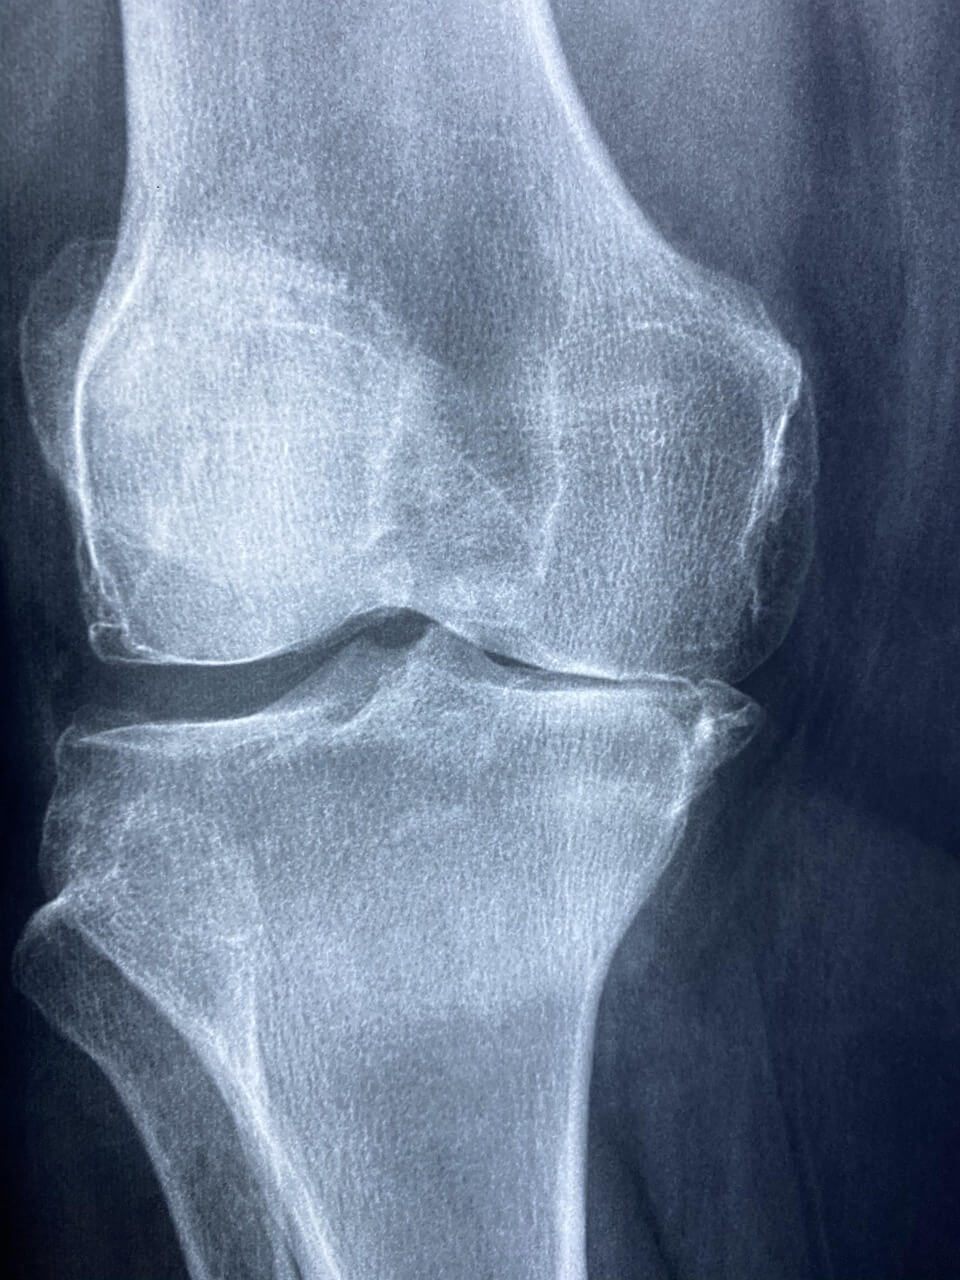

보건복지부는 노인성 퇴행성 관절염으로 인해 무릎 통증을 겪는 고령자를 대상으로 ‘노인 무릎 인공관절 수술 지원사업’을 운영하고 있습니다.

이 사업은 경제적으로 수술이 어려운 저소득층 시니어에게 무릎 인공관절 수술비를 최대 120만 원까지 지원하는 제도입니다.

- 진단 기준: 정형외과 전문의의 인공관절 수술 필요 소견